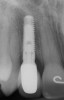

Figure 5h  Postoperative radiographs.

Figure 5h

Figure 5g  Postoperative radiographs.

Figure 5i

Figure 5a  Congenitally missing lateral incisors. Postorthodontic therapy, prior to implant placement.

Figure 5a

Figure 5b  Congenitally missing lateral incisors. Postorthodontic therapy, prior to implant placement.